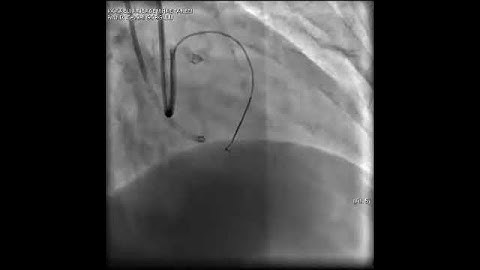

Aortic dissection and radial rupture during retrograde CTO PCI: Management of complications VİDEO 22